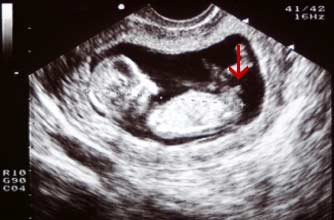

(男宝)

Boy nub: The nub is at a much steeper angle upwards, indicating that this baby is a boy.

小肿块以一个陡峭的角度向上指,显示这个胎儿是个男孩。